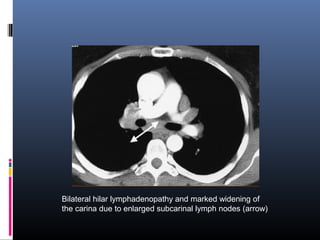

Bilateral hilar lymphadenopathy and marked widening of

the carina due to enlarged subcarinal lymph nodes (arrow)

Bilateral hilar lymphadenopathyand marked widening of the carina due to enlarged subcarinal lymph nodes (arrow)

• #35 Chest CT scan from the same patient following intravenous contrast. Bilateral hilar lymphadenopathy and marked widening of the carina due to enlarged subcarinal lymph nodes (arrow) are present